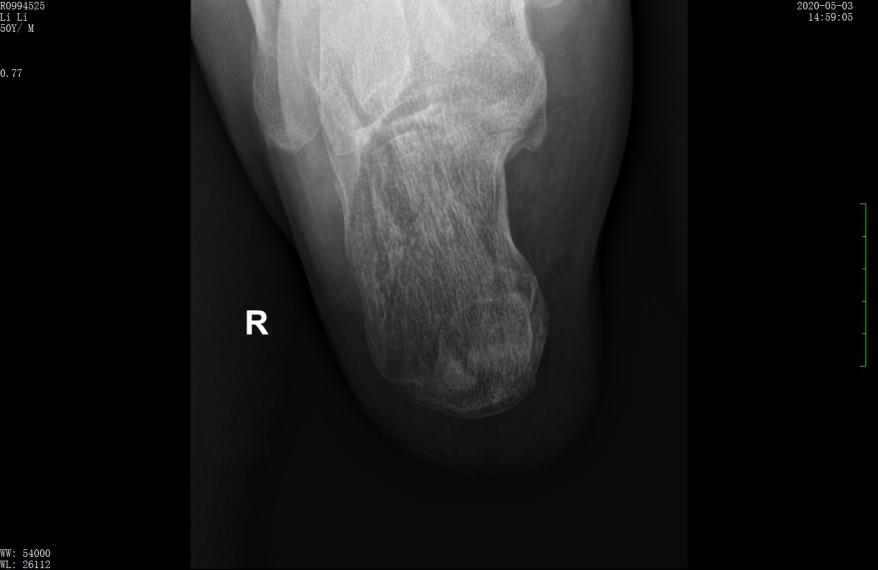

术前CT示跟骨严重粉碎骨折,移位明显